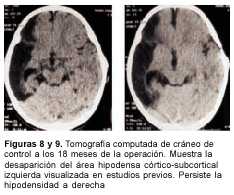

A los 3 meses de edad consultó por hemiplejia izquierda y retraso psicomotor. La tomografía computada (TC) de cráneo demostró un infarto hemisférico derecho (figura 1). Los estudios complementarios pusieron de manifiesto una coartación de aorta torácica descendente, sin evidencia de patología arterial sistémica. A nivel encefálico se estudió con angiografía de cuatro vasos de cuello, que demostró la existencia de una enfermedad de moyamoya (figuras 2 a 4). En ese momento no se consideró el tratamiento quirúrgico y una vez estabilizada se otorgó el alta. La coartación de la aorta no requirió cirugía y no se investigó el eventual nexo con la enfermedad de moyamoya. A los 8 meses de edad comenzó con hemiparesia derecha progresiva, lo que junto a su hemiplejia izquierda agravó su déficit motor severamente. Ingresó al Centro Hospitalario Pereira Rossell a los 10 meses. El examen del ingreso mostraba retardo neuropsíquico, hemiplejia izquierda espástica y hemiparesia derecha severa, que apenas vencía gravedad y no oponía resistencia. Una nueva TC mostró como elemento agregado al infarto derecho previo, una isquemia hemisférica izquierda (figura 5). Se resolvió realizar una revascularización quirúrgica del hemisferio izquierdo. Se intervino (figura 6) en el Servicio de Neurocirugía Pediátrica del Hospital. El procedimiento realizado fue una pialsinangiosis, con disección de la arteria temporal superficial izquierda con galea satélite y la sutura del tejido periarterial a la aracnoides temporal. La evolución posoperatoria fue buena, con recuperación progresiva de la función motora del hemicuerpo derecho. En forma gradual también comenzó a recuperar motricidad de su hemicuerpo izquierdo, anteriormente pléjico, y a mejorar sus performances, comenzando a pronunciar palabras a los cuatro meses, aunque manteniendo un retraso en el desarrollo psicomotor. Al año de operada se constató leve hemiparesia izquierda, ausencia de elementos deficitarios motores a derecha y persistencia de alteraciones en el lenguaje. Una ARM realizada a los diez meses de la operación mostró desarrollo de circulación colateral hacia el área quirúrgica (figura 7). Una TC de control permitió ver el infarto secuelar de hemisferio derecho y disminución franca de la hipodensidad del hemisferio izquierdo a los 18 meses de operada (figuras 8 y 9).

El resultado favorable de la técnica quedó efectivamente evidenciado en los estudios imagenológicos hechos 10 y 18 meses después de la cirugía, ya que la RM mostró desarrollo de circulación colateral hacia el área quirúrgica y la TC una disminución del territorio isquémico a izquierda.

Paralelamente hubo no sólo una detención del progresivo deterioro motriz que presentaba la paciente hasta el momento de la cirugía, sino que, por el contrario, tuvo una mejoría clara del punto de vista motor. Si bien la vinculación de la remisión tomográfica y de la mejoría clínica con el procedimiento quirúrgico son discutibles, no sucede lo mismo con la mejoría de la vascularización, por lo que es lícito atribuir el resultado global a la cirugía, confirmando la experiencia de otros autores.

Figuras 8 y 9. Tomografía computada de cráneo de control a los 18 meses de la operación. Muestra la desaparición del área hipodensa córtico-subcortical izquierda visualizada en estudios previos. Persiste la hipodensidad a derecha